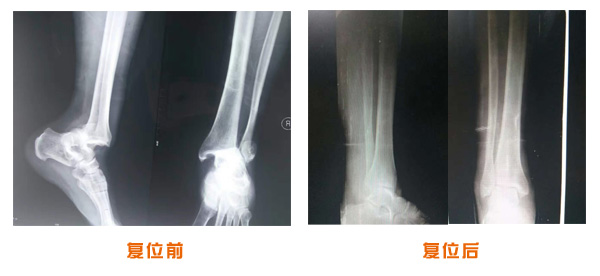

復位前后對比

踝關節脫位骨折治療前后對比